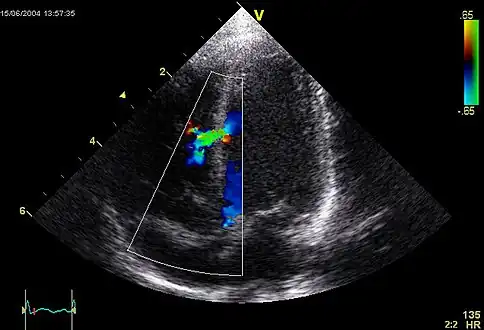

![]() An abnormal echocardiogram: Image shows a midmuscular ventricular septal defect. The trace in the lower left shows the cardiac cycle and the red mark the time in the cardiac cycle when the image was captured. Colors are used to represent the velocity and direction of blood flow. | |

Echocardiography can help detect cardiomyopathies, such as hypertrophic cardiomyopathy, dilated cardiomyopathy, and many others. The use of stress echocardiography may also help determine whether any chest pain or associated symptoms are related to heart disease. The biggest advantage of echocardiography is that it is not invasive (does not involve breaking the skin or entering body cavities) and has no known risks or side effects.[6] Not only can an echocardiogram create ultrasound images of heart structures, but it can also produce accurate assessment of the blood flowing through the heart by Doppler echocardiography, using pulsed- or continuous-wave Doppler ultrasound. This allows assessment of both normal and abnormal blood flow through the heart. Color Doppler, as well as spectral Doppler, is used to visualize any abnormal communications between the left and right sides of the heart, any leaking of blood through the valves (valvular regurgitation), and estimate how well the valves open (or do not open in the case of valvular stenosis). The Doppler technique can also be used for tissue motion and velocity measurement, by tissue Doppler echocardiography.